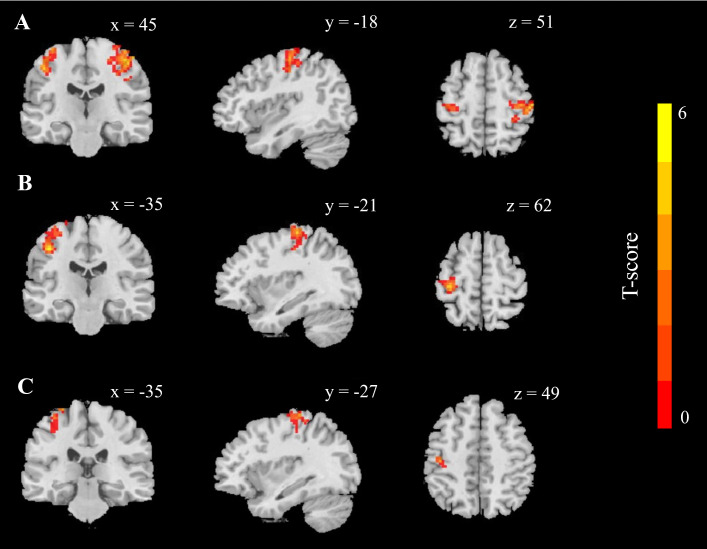

Results: The BMI, glucose and insulin concentrations, insulin resistance, and anxiety scores significantly decreased during and after fasting compared to the baseline measurements (all p < 0.05), lasting for two months. Furthermore, we used the bilateral laterobasal amygdala as seed regions, which are responsible for emotional regulation and anxiety-like behaviours; we found changes in resting-state connectivity with the postcentral gyrus on fasting days 30 and 50.

Conclusion: IF reduces anxiety by modulating amygdala functional connectivity and enhancing brain plasticity, suggesting its potential as a therapeutic approach for anxiety and related emotional disorders. The findings underscore IF's promise as an alternative or adjuvant intervention in psychiatric care.